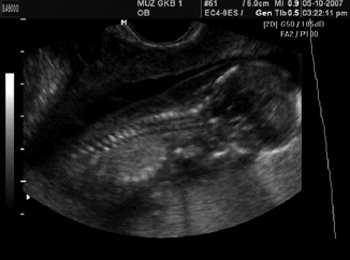

При эхокардиографии изучались четырехкамерный срез сердца плода (рис. 1) и срез через три сосуда (рис. 2). УЗИ проводилось трансабдоминальным датчиком, лишь при необходимости (затрудненная визуализация) использовался внутриполостной датчик. Четырехкамерный срез сердца плода при ультразвуковом сканировании трансабдоминальным датчиком визуализировался в 85% случаев, срез через сосуды - в 73%, при использовании трансвагинального датчика эти цифры существенно возрастали до 100 и 91% соответственно. Оптимизация пренатальной диагностики ВПС может быть достигнута путем строгого соблюдения основных методических правил. При оценке четырехкамерного среза плода необходимо оценить нормальное расположение сердца плода, исключив его эктопию (рис. 3), положение оси сердца плода, что не представляет никаких трудностей, нормальные пропорции и размеры камер сердца, движение створок атриовентрикулярных клапанов должно быть свободным, септальная створка трикуспидального клапана должна располагаться ближе к верхушке сердца (рис. 4). При оценке среза через три сосуда необходимо оценить взаиморасположение сосудов и их диаметр.